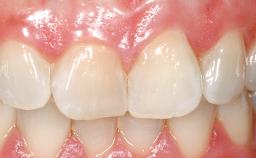

A 36-year-old female patient was referred for the replacement of the upper left central incisor (tooth 21), which had fractured. Although the tooth had been asymptomatic for many years, the crown began to loosen, at which time she presented to her dentist for an assessment. Teeth 21 and 22 had both been endodontically treated many years previously. She was a healthy individual and a non-smoker.

On examination, the patient had a low lip line and only displayed the coronal half of the anterior teeth when smiling.

SAC Level | Advanced |

Defining Characteristics | One missing tooth to be replaced by an implant-borne crown |